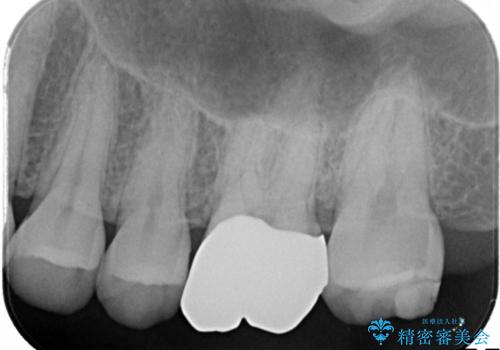

【メタルフリー】銀歯を白くしたい。オールセラミッククラウン。

- 銀歯を白くしたいと希望され来院されました。

すぐにでも白くしたいとのことで、2回目の来院で銀歯を白い仮歯に変更し喜んでいただきました。

ただ単純に白くするでけではなく拡大鏡を使用し、丁寧な処置を行なっております。